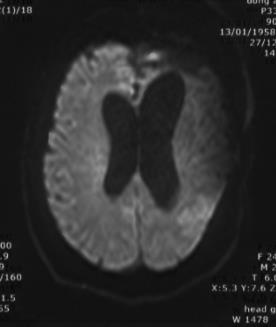

复阅2018年12月27日MRI片:左侧额颞部颅骨修补术后改变,两侧额颞叶、右侧小脑半球、左侧侧脑室后角旁均见长T1长T2异常信号,脑室系统扩大。提示左侧额颞部颅骨修补术后,两侧额颞叶、右侧小脑半球、左侧侧脑室后角旁软化灶形成。

图7-12,2018年12月27日MRI片,左侧额颞部颅骨修补术后,两侧额颞叶、右侧小脑半球、左侧侧脑室后角旁软化灶形成